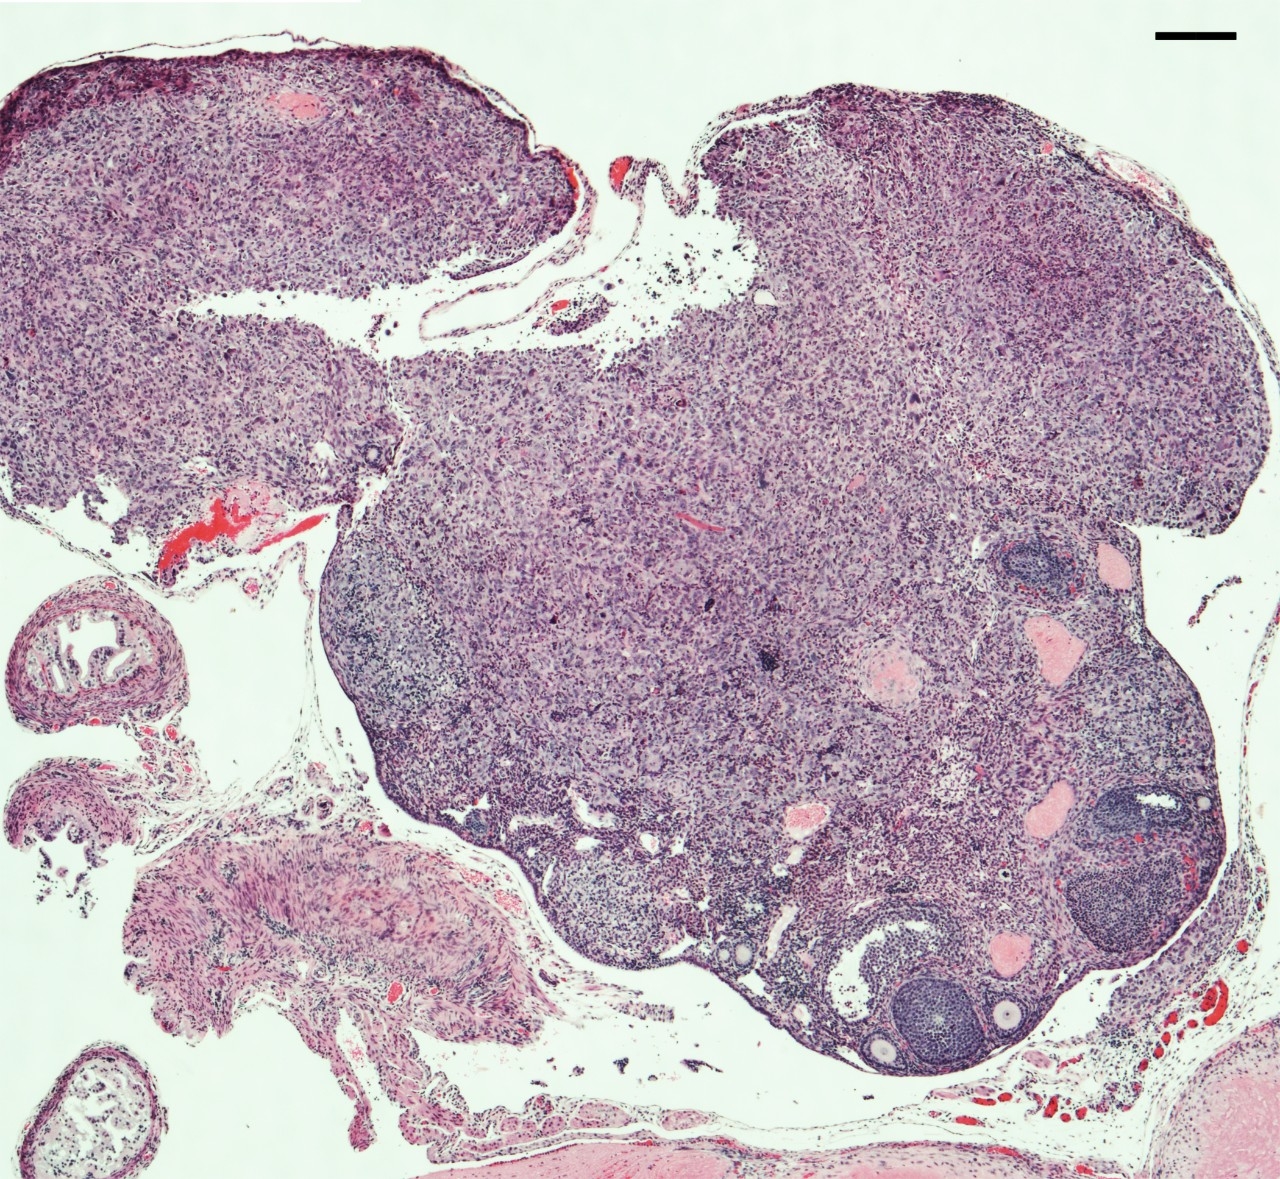

The Zhang Laboratory studies ovarian cancer biology with the goal of developing novel therapeutic approaches to combat the disease with precision. The ultimate goal of this line of investigation is to leverage the newly gained mechanistic insights for developing new therapeutics in a personalized manner based on one’s unique genetic and/or pathway signatures.

- Ovarian Cancer

- Fallopian Tube Cancer